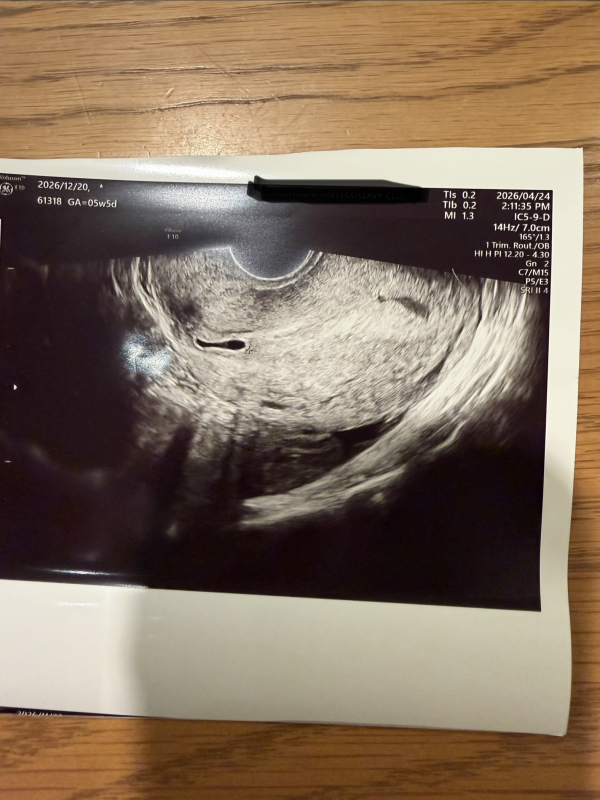

昨日、5w5d(最終月経からの計算です)で病院に行きました。 胎嚢らしきものは見えたのですが、位置が通常よりも左寄りすぎること、形もいびつであることから、来週の火曜日にまた受診予定となりました。

今までの妊娠では、真ん中あたりに胎嚢が見えていたので、こんなに左にあることに不安を感じます。形もいびつなため、余計に不安です。 先生は、「たぶんこれが胎嚢だと思うけど、、う〜ん…」という、悩んだ感じでした。

このように、胎嚢が左側に見えることもあるのでしょうか? その後の診察で、真ん中あたりに見えるようになることはあるのでしょうか?

また、このようにいびつな形だと、流産に繋がってしまうのでしょうか? 不安な気持ちが大きく、落ち着きません。。

胎嚢の位置や形について、医師から気になると指摘があったのですね。確かに、胎嚢の形が歪であったりする場合には、正常に妊娠が起こっていないケースもあり、心拍が確認できず、流産になってしまうこともあります。

実際にみっふぃーさんのエコーを拝見していませんので、ハッキリとしたことは明言できませんが、経過を見ていく中で、形が少しずつ変化してくることもありますし、心拍が確認できれば問題ないことも多いので、今はなんとも言えない時期ではありますが、まずは赤ちゃんの生きる力を信じてあげてくださいね。